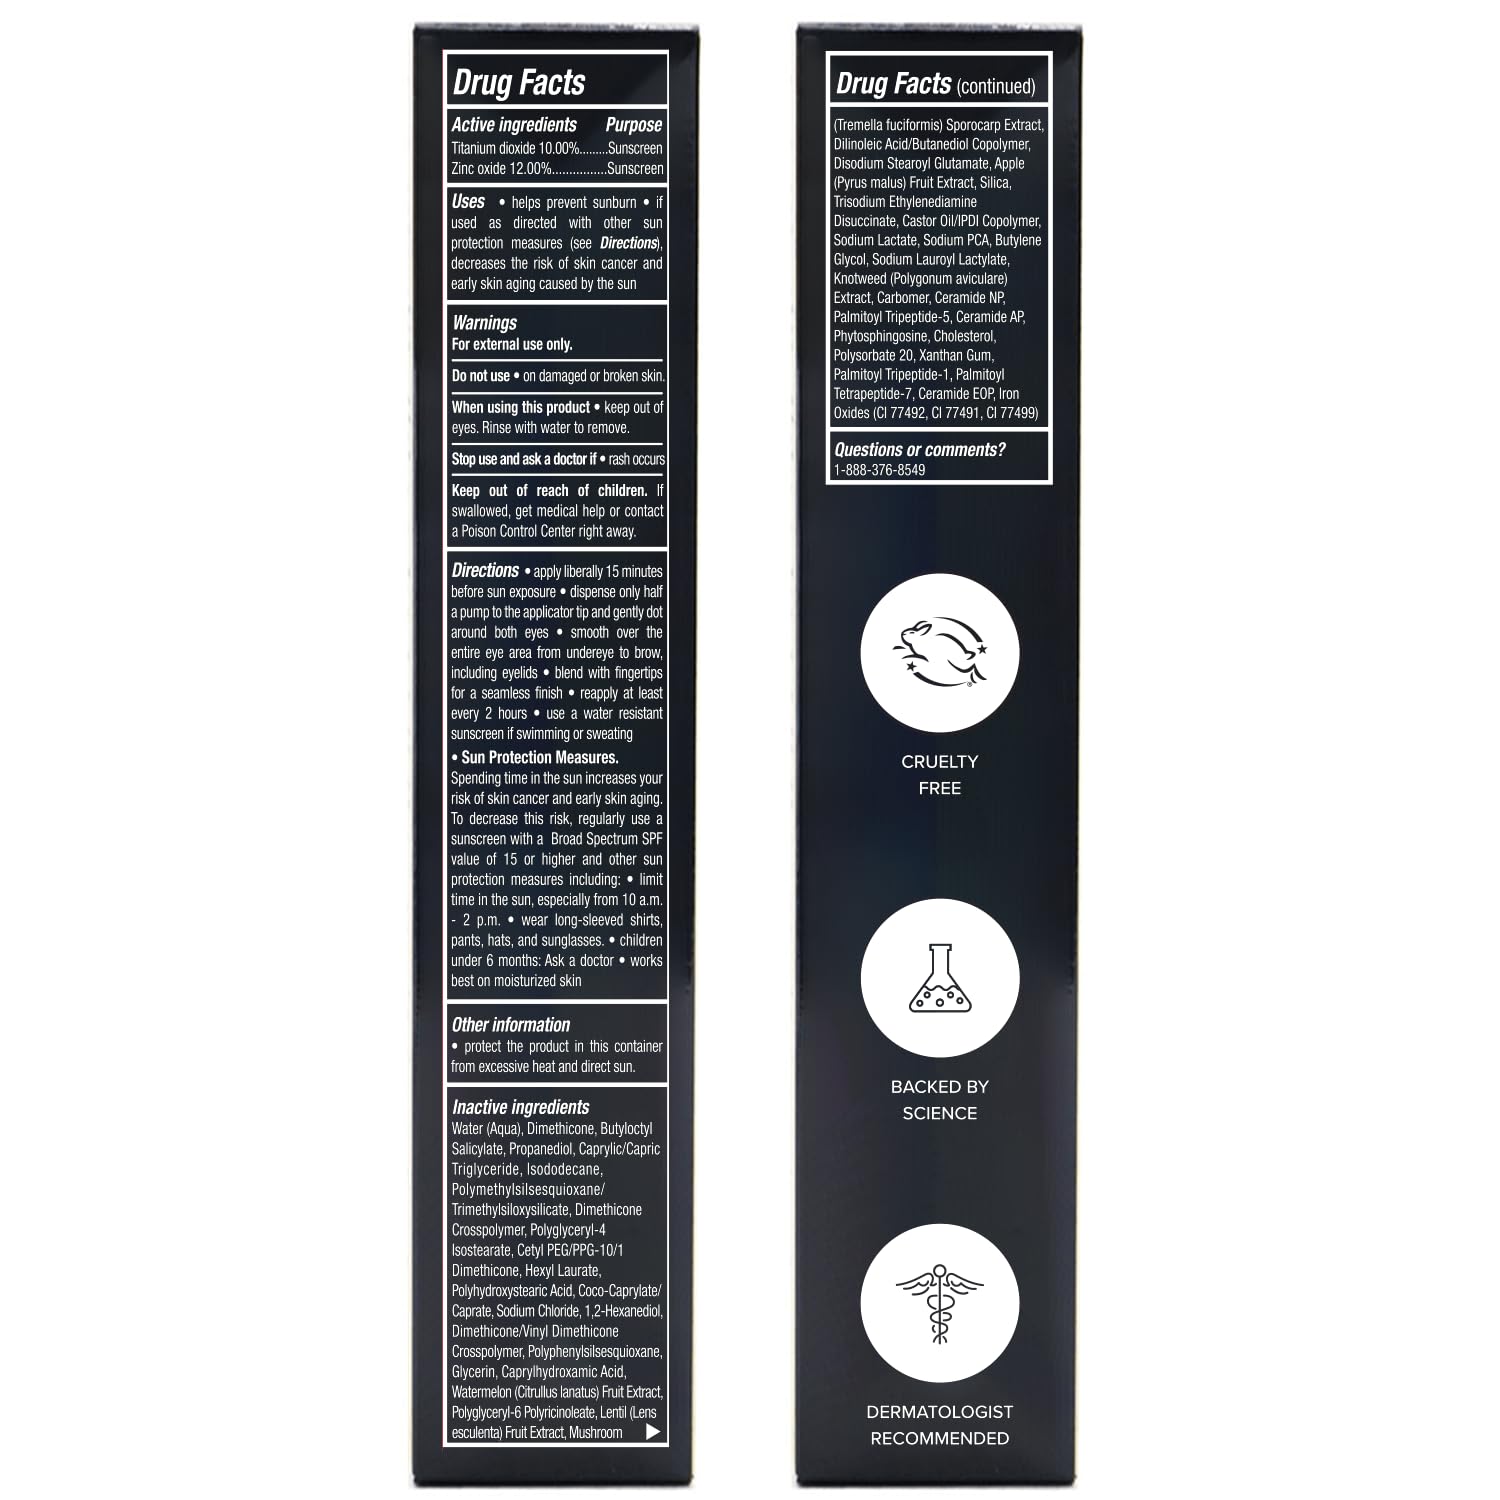

Our eye corrector for dark circles is powered by anti-aging ingredients including peptides, snow mushroom, and ceramides. It is hydrating and firms the look of fine lines, providing effective puffy eye treatment. It's also free of parabens, sulfates, gluten, sulfate, cruelty and fragrance.

Astaxanthin - It has been shown to have numerous benefits for the skin, including reducing inflammation, protecting against oxidative stress, and improving skin elasticity. When applied topically astaxanthin can help to promote a more youthful and radiant complexion by minimizing the appearance of fine lines and wrinkles, improving skin texture and tone, and protecting the skin from damage caused by UV radiation and other environmental factors.

Squalane is a multi-functional ingredient that offers various benefits for the skin, which include improving the skin barrier function,When used on the eye area, Vaseline provides a brightening effect that can help diminish the appearance of dark circles,Effectively resist oxidationImprove eye dullness, leaving the skin around the eyes looking more radiant, even-toned, and youthful.

Shea butter has excellent moisture-retaining ability that helps hydrate and plump the skin. When applied to the eye area, it provides intense hydration and moisture, diminishing the appearance of fine lines and wrinkles while improving the overall texture and tone of the skin.

- Core ingredients: Retinol Extract, Squalane, Astaxanthin, Shea butter